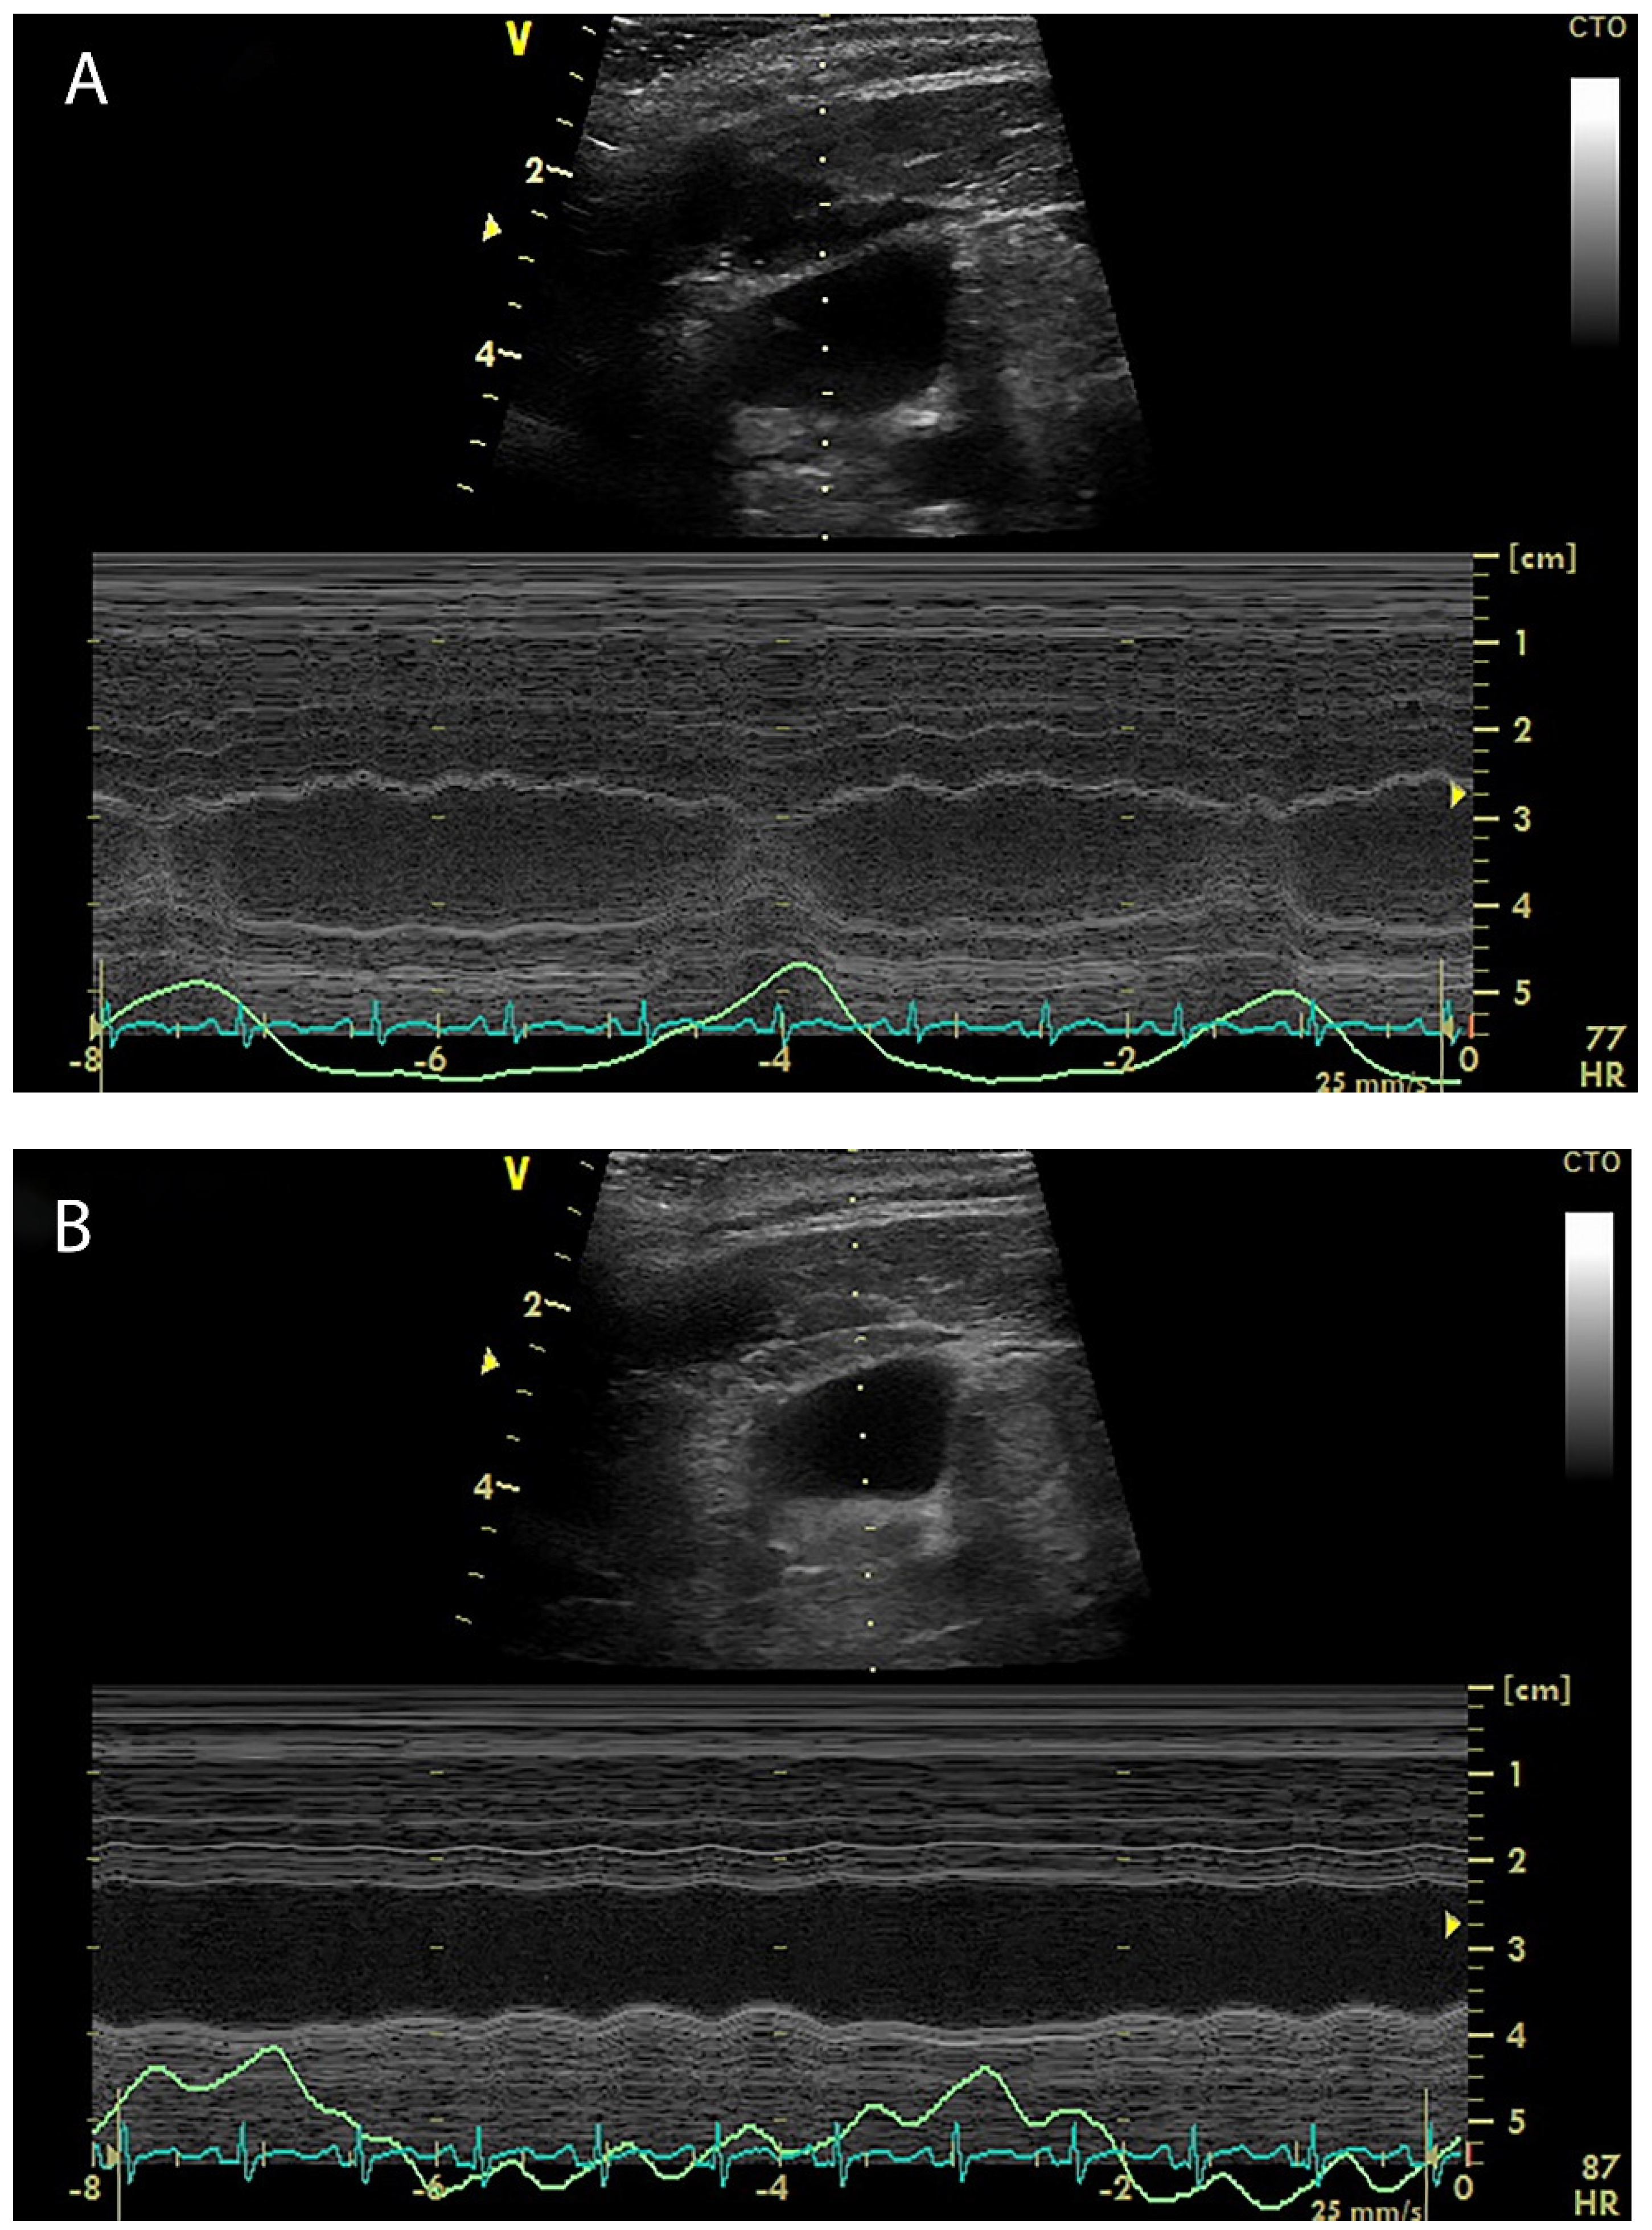

4. Internal Jugular Vein Distensibility